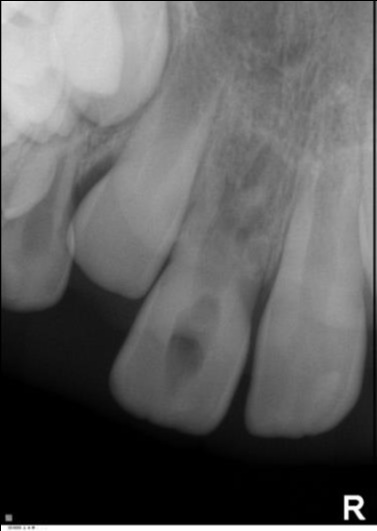

Ursachen und Therapie von Frontzahnlücken im jugendlich-bleibenden Gebiss

Ursachen für Frontzahnlücken

Fallbeispiele direkt aus der Praxis